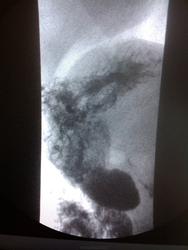

Пациент, 60 лет. На ФГДС: В антральном отделе отмечается некоторая ригидность на малой кривизне, рядом с привратником.

Не вижу изменений в антральном отделе, но обращает внимание некоторая ригидность задне-медиальной стенки субкардиально.

Обратила внимание на уплощение контура на малой кривизне препилорического отдела. Но только на одном снимке, на остальных - без особенностей. Вряд ли стоит придавать этому значение. Вы видели моторику - Вам судить

Ригидность стенки, и не только на мой взгляд, оценивается в процессе просвечивания.